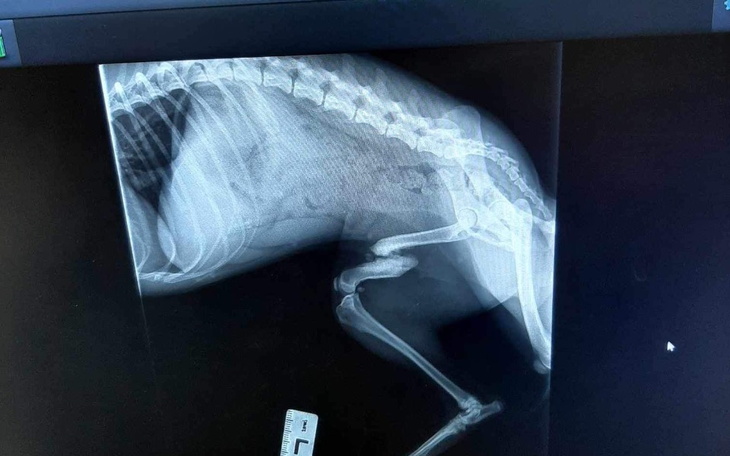

Czas przedstawić Fifi. Suczka bytowała na stacji cpn, najprawdopodobniej tam została potrącona. I tak ze złamaną nogą bytowała dalej na ulicy.Kiedy trafiła pod opiekę Piotra miała anaplazmoze - chorobę odkleszczową i na tym trzeba było początkowo się skupić.Kiedy trafiła do Zacisza nadal utykała. Zostały wykonane zdjęcia rtg i okazało się, że złamanie jest stare, częściowo zrośnięte, ale noga jest krótsza i może jej doskwierać przez resztę życia dlatego została podjęta decyzja o operacji.

Zabieg się udał, teraz staje na rzęsach, żeby przyprawić mnie o zawał próbując brykać pomimo zakazu lekarza!Po 6/8 tygodniach zostaną usunięte druty i ta młoda, radosna dziewczyna będzie mogła ruszać w świat!